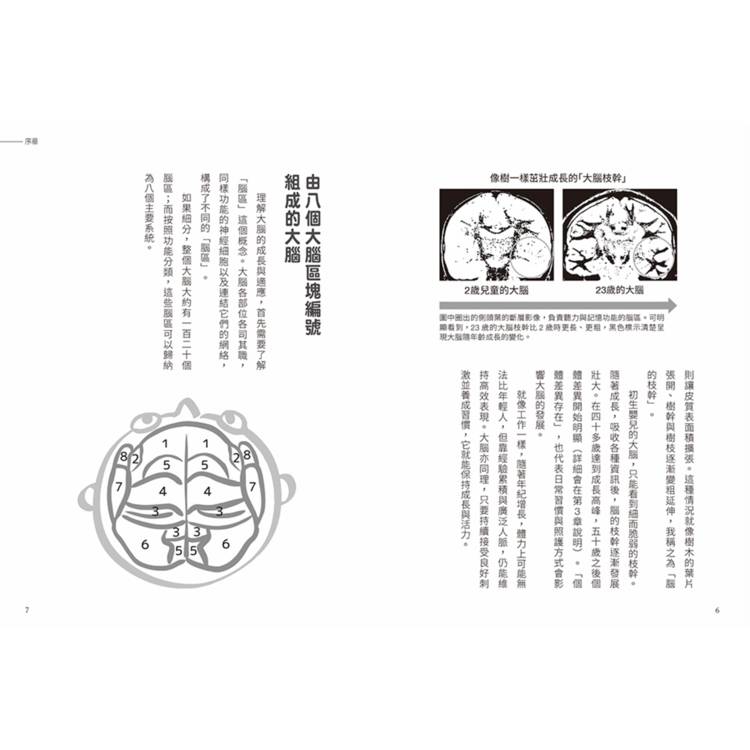

持續成長的大腦

我在一九八七年從醫學院畢業後,一邊累積各種臨床經驗,一邊進行 MRI 腦影像的獨自診斷研究。透過分析從胎兒到百歲以上高齡者、超過一萬人的腦影像,我得出了一些重要的發現:

• 大腦每天都在變化,直到死亡前都能持續成長。

• 沒有兩個人擁有完全相同的大腦,每個大腦都是其人生經驗的總和。

雖然神經細胞的數量從一歲前就開始減少,但大腦中的胺基酸分泌並不會隨年齡下降。「生命之源」般的胺基酸,是構成身體不可或缺的營養成分,也是大腦的重要養分。只要營養持續供給,大腦就具備持續成長的潛力。這些觀察結果帶給我們一些重要啟示,「大腦成長」並不僅取決於神經細胞的數量,更重要的是細胞間的網絡。具體而言,神經細胞聚集的「皮質」與神經纖維聚集的「白質」網絡被強化,這才是真正的大腦成長方式。即便隨著年齡神經細胞數量減少,大腦網絡仍能不斷增強,從而維持大腦功能。

當大腦獲得資訊刺激時,負責傳遞訊息的白質會變得更粗壯,而處理資訊的神經細胞成長則讓皮質表面積擴張。這種情況就像樹木的葉片張開、樹幹與樹枝逐漸變粗延伸,我稱之為「腦的枝幹」。初生嬰兒的大腦,只能看到細而脆弱的枝幹。隨著成長,吸收各種資訊後,腦的枝幹逐漸發展壯大。在四十多歲達到成長高峰,五十歲之後個體差異開始明顯(詳細會在第 3 章說明)。「個體差異存在」,也代表日常習慣與照護方式會影響大腦的發展。就像工作一樣,隨著年紀增長,體力上可能無法比年輕人,但靠經驗累積與廣泛人脈,仍能維持高效表現。大腦亦同理,只要持續接受良好刺激並養成習慣,它就能保持成長與活力。

持續成長的大腦

我在一九八七年從醫學院畢業後,一邊累積各種臨床經驗,一邊進行 MRI 腦影像的獨自診斷研究。透過分析從胎兒到百歲以上高齡者、超過一萬人的腦影像,我得出了一些重要的發現:

• 大腦每天都在變化,直到死亡前都能持續成長。

• 沒有兩個人擁有完全相同的大腦,每個大腦都是其人生經驗的總和。

雖然神經細胞的數量從一歲前就開始減少,但大腦中的胺基酸分泌並不會隨年齡下降。「生命之源」般的胺基酸,是構成身體不可或缺的營養成分,也是大腦的重要養分。只要營養持續供給,大腦就具備持續成長的潛力。這些觀察結果帶給我們一些重要啟示,「大腦成長」並不僅取決於神經細胞的數量,更重要的是細胞間的網絡。具體而言,神經細胞聚集的「皮質」與神經纖維聚集的「白質」網絡被強化,這才是真正的大腦成長方式。即便隨著年齡神經細胞數量減少,大腦網絡仍能不斷增強,從而維持大腦功能。

當大腦獲得資訊刺激時,負責傳遞訊息的白質會變得更粗壯,而處理資訊的神經細胞成長則讓皮質表面積擴張。這種情況就像樹木的葉片張開、樹幹與樹枝逐漸變粗延伸,我稱之為「腦的枝幹」。初生嬰兒的大腦,只能看到細而脆弱的枝幹。隨著成長,吸收各種資訊後,腦的枝幹逐漸發展壯大。在四十多歲達到成長高峰,五十歲之後個體差異開始明顯(詳細會在第 3 章說明)。「個體差異存在」,也代表日常習慣與照護方式會影響大腦的發展。就像工作一樣,隨著年紀增長,體力上可能無法比年輕人,但靠經驗累積與廣泛人脈,仍能維持高效表現。大腦亦同理,只要持續接受良好刺激並養成習慣,它就能保持成長與活力。